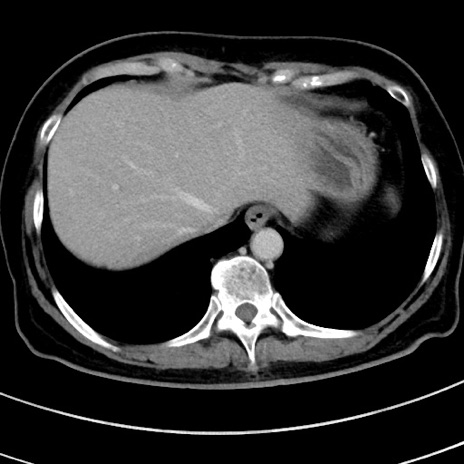

症例9(横断像)

【症例】 60歳代女性

【主訴】むかつき、みぞおちの痛み

【現病歴】3日前よりむかつきがあり、食事がとれない。

【既往歴】糖尿病

【身体所見】発熱なし、心窩部圧痛軽度あるも、腹膜刺激症状なし。

【データ】WBC 7400、CRP 1.92